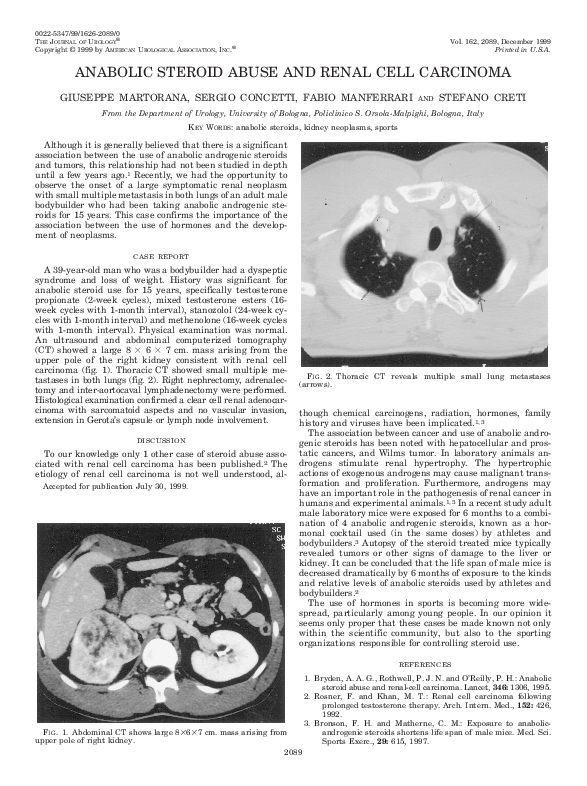

(PDF) Anabolic steroid abuse and renal cell carcinoma F. Manferrari Academia.edu Steroids And Kidney Cancer Treatment of stage iv kidney cancer depends mainly on how extensive the cancer is and on a person’s general health. Steroids are manufactured versions of hormones that help control many body functions. This review article discusses the link between kidney disease and cancer, and the effects of chemotherapy on renal function. You understand more about kidney cancer. They can treat. Steroids And Kidney Cancer.